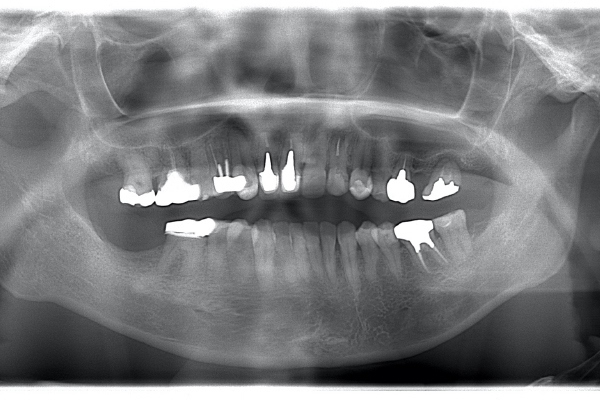

| 治療方針 | 全体的に10年以上前の治療痕で、銀歯の下でカリエスになっています。今回は右上5に限っての方針を記載する。 |

カリエスを取り除くと、遠心の歯質が歯肉縁下になりました。

左上2は広範囲にわたってCRが充填されているのがわかります。またその周囲に透過像があり、カリエスになっていることもわかります。